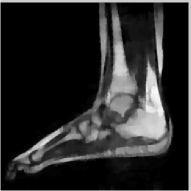

The reconstructions of an ankle image from its 4 fold Cartesian undersampled Fourier data, corrupted with zero mean complex Gaussian noise with a standard deviation σ=10𝜎10\sigma=10, are shown in Fig. 5. This is a really challenging case since the 1-D downsampling pattern is considerably less efficient than the 2-D random pattern used in the previous experiment. We observe that the non-local algorithm provides better reconstructions than the other schemes. Specifically, the TV scheme results in patchy artifacts. The DLMRI scheme results in blurring and loss of details close to the heel. The details are relatively better preserved close to the finger since there are no structures above or below it that aliases to it. By contrast to the classical algorithms, the degradation in performance of the non-local algorithm is comparatively small. The quantitative comparisons of the algorithms on this setting using different images are shown in the top section of Table IV.

Refer to caption

(a) Original

(b) DLMRI, SNR=12.96

(c) TV, SNR=15.02

(d) NLS, SNR=18.52

(e) Sampling pattern

(f) DLMRI error

(g) TV error

(h) NLS error

Figure 5: Comparison of the algorithms in the presence of noise. We consider the recovery of a 256×256256256256\times 256 MRI ankle image from its Cartesian Fourier sampling pattern (shown in (e)), contaminated by zero mean complex Gaussian noise with standard deviation σ=10𝜎10\sigma=10. The top row shows the original and reconstructed images, while the error images scale by a factor of five are shown in the bottom row. This is a challenging case due to the high 1-D undersampling factors and noise. We observe that the NLS scheme provides the best reconstructions with minimal alias artifacts.